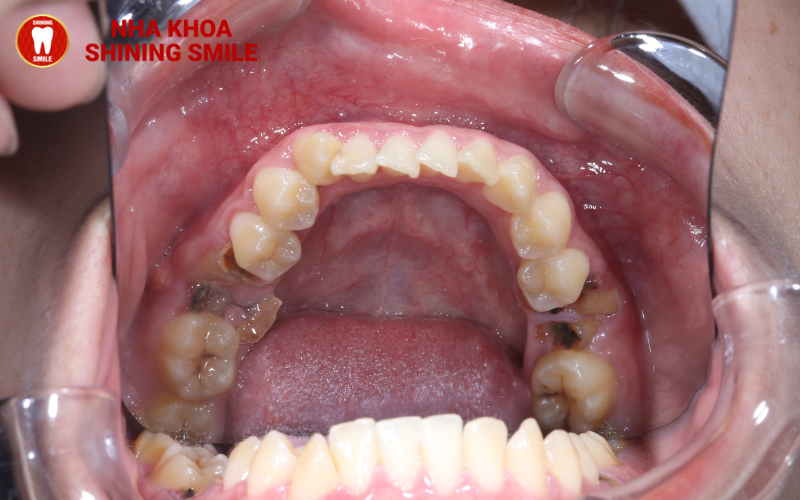

Cấy ghép implant là giải pháp hàng đầu trong việc phục hình răng đã mất với hiệu quả vượt bậc. Với khả năng mang tới kết quả răng tồn tại trọn đời, cấy ghép implant chính là giải pháp được ưa chuộng nhất hiện nay trong việc trồng răng. Tuy nhiên, vì một số lý do, răng implant sau khi trồng có thể rơi vào trạng thái bị đào thải. Vậy nguyên nhân là gì và phải làm sao khi răng implant bị đào thải? Tất cả các vấn đề sẽ được giải quyết trong bài viết dưới đây cùng nha khoa Shining Smile.